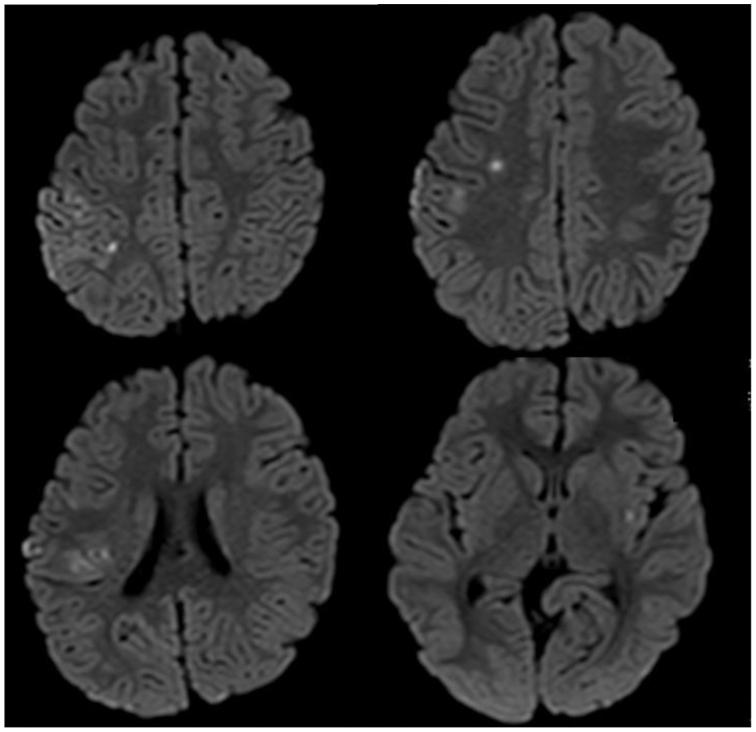

A 4-year-old girl presented with complaints of transient speech disorder and left-sided weakness. Magnetic resonance imaging revealed multiple strokes, computed tomography showed a right axillary artery aneurysm of 40 mm, and an angiogram indicated retrograde embolism. She underwent aneurysm resection and reconstruction with a saphenous vein graft. Two years after surgery, a mass lesion occurred in the native artery on the proximal side of the prior surgical anastomosis. Surgical resection and reconstruction were performed. An isolated 1-mm diameter lesion was found in the retrospectively reviewed completion angiogram from the initial surgery, which was the origin of the subsequent progressive lesion. The pathological examination, including after the initial surgery, revealed a myopericytoma.

摘要

一名4岁女孩因短暂性言语障碍和左侧肢体无力前来就诊。磁共振成像显示多处中风,计算机断层扫描显示右腋动脉有一个40毫米的动脉瘤,血管造影显示逆行栓塞。她接受了动脉瘤切除并用大隐静脉移植进行重建。术后两年,在先前手术吻合口近端的原动脉处出现了一个肿块病变。进行了手术切除和重建。在对初次手术的回顾性完成血管造影中发现了一个直径1毫米的孤立病变,这是随后进展性病变的起源。包括初次手术后的病理检查显示为肌周细胞瘤。